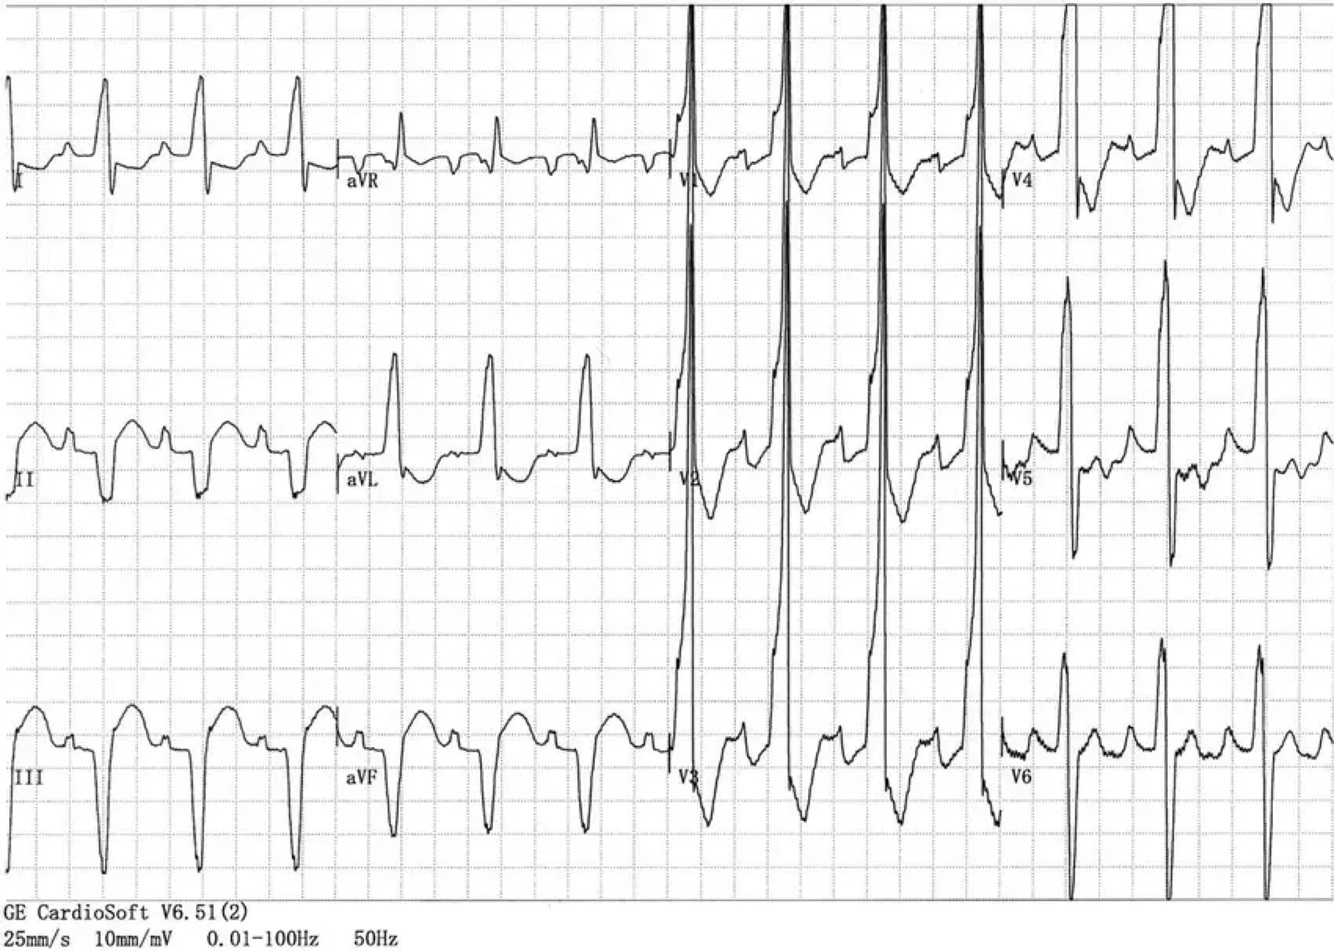

⛔️BLOQUEIO🎭MASCARADO  :

BDR em precordiais

➕

BRE em D1 sem onda S

⛔️BLOQUEIO MASCARADO 🎭:

▪️presença de morfologia característica de BRD no plano horizontal (V1-V6)

ASSOCIADO a morfologia de BRE c/desvio do eixo p/esquerda no plano frontal (DI ,aVL)

▪️Este tipo de BRD é causado pela associação simultânea com BDAS de alto grau frequentemente acompanhado por SVE grave🏋️‍♂️

E/OU Bloqueio Focal 🎯da parede anterolateral do VE devido a infarto do miocárdio ou fibrose.

▪️Na maioria dos casos típicos de BRD

c/BDAS, o eixo elétrico 🧭 no plano frontal encontra-se entre -80° e -120°, ENTRETANTO, ⚠️

quando o eixo permanece próximo a -60°,devido ao predomínio de forças ventriculares esquerdas,

o BRD c/ BDAS será acompanhado que onda “S” muito pequena OU AUSENTE em D1, simulando o padrão de BRE nesta derivação.

▪️O BRD com BDAS pode imitar o BRE tanto nas derivações dos membros (mascaramento padrão) com

🚫AUSÊNCIA de onda “S” em D1, quanto nas derivações precordiais (mascaramento precordial) com

🚫DESAPARECIMENTO da

onda “S” em V5 e V6.

▪️Em ambos os casos o BRD pode ser reconhecido pelo seu padrão típico em V1.

▪️Vale ressaltar que este padrão está associado a pior prognóstico e implica doenças subjacentes graves.

🧨Ex: risco de evoluir com BAVT em 1-2 anos é 20-30%